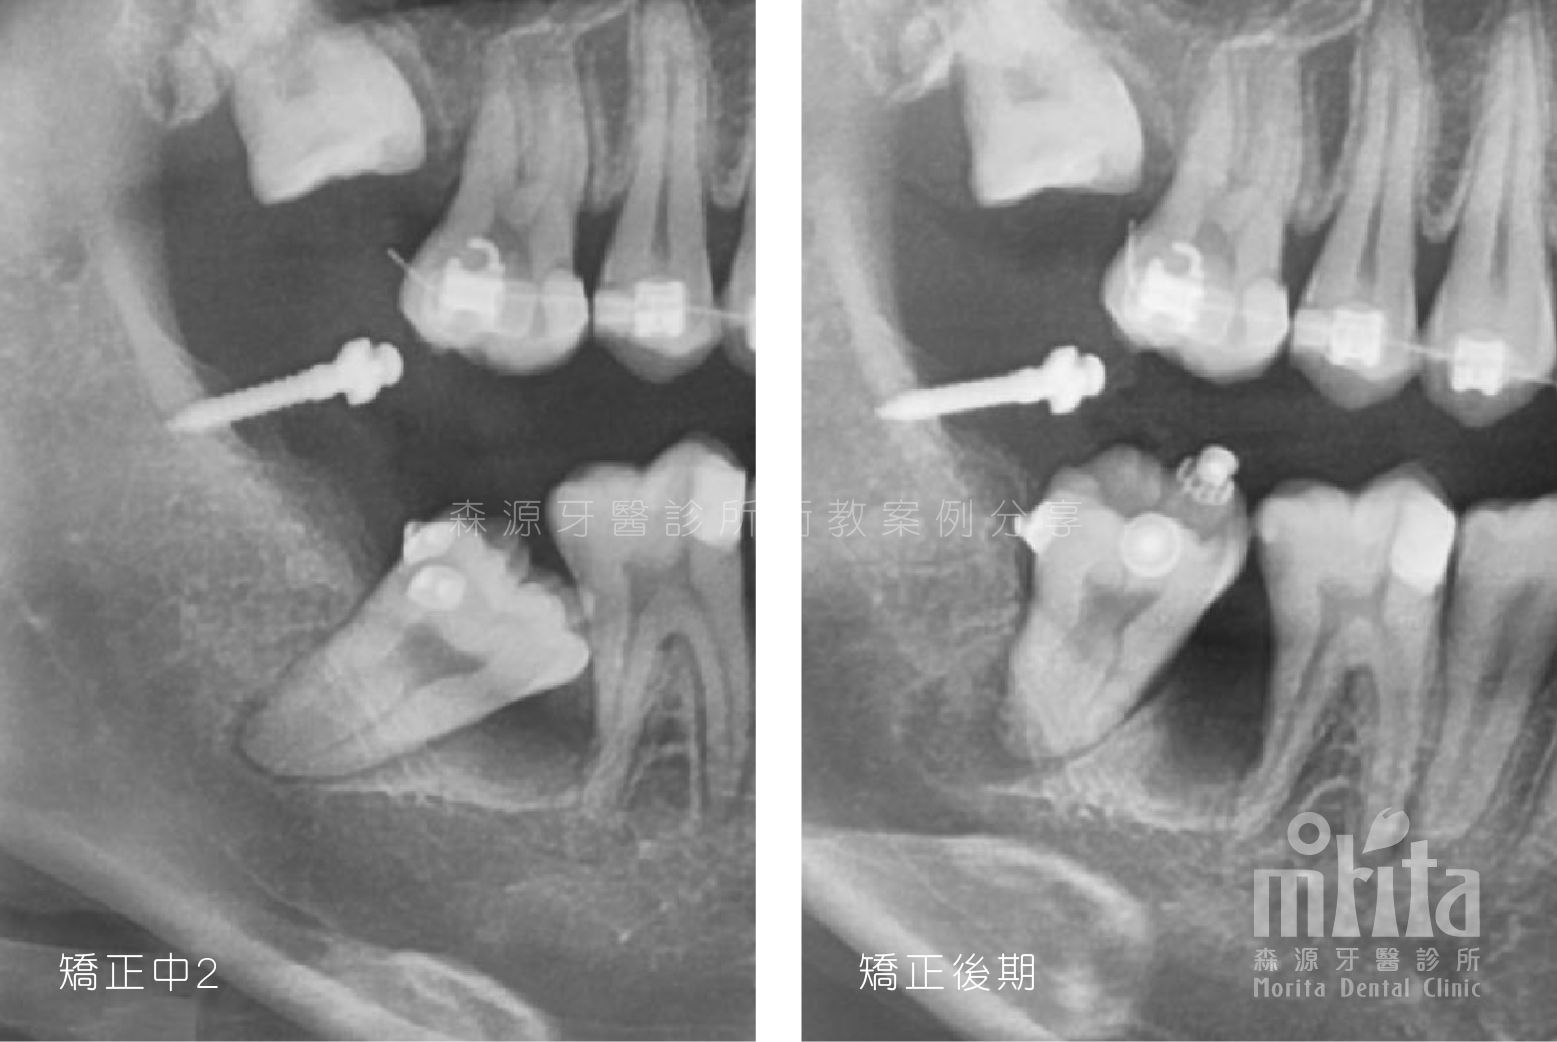

阻生齒 Impaction

可能因為過早地缺牙,可能因為齒列過於擁擠,又或是老天爺開的玩笑,造成有些該⻑出來的牙齒⻑不出來,需要在阻生齒還有生⻑潛力時拉一把,讓牙齒順利萌發。